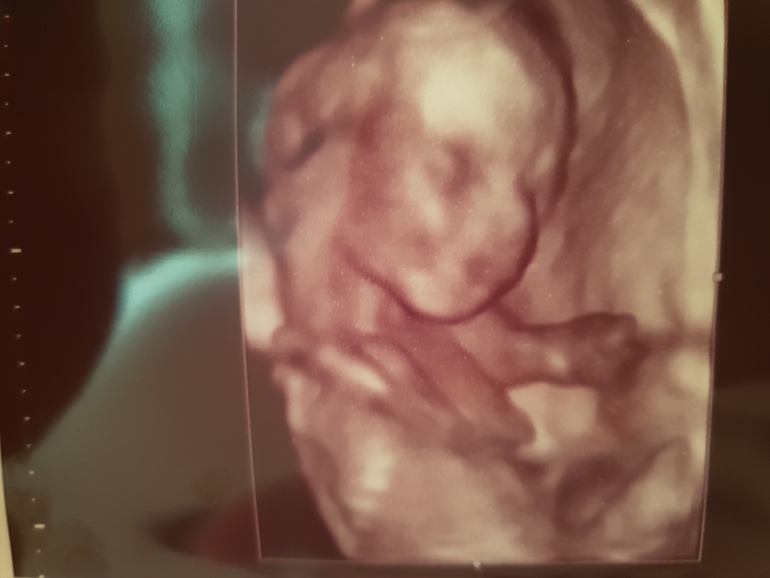

Сегодня была на втором скрининге, самое главное всё хорошо!!!очень дотошно смотрела врач, в целом минут 40!!!см отрели и через живот и вагинально...вес 314 гр)носовая кость 5.6 мм,147 удров сердечко)))и пол подтвердила-девочка)!!! Вот и пол пути пройдено...когда смотрю назад понимаю, что время летит со скоростью света!!!

наше чудо!